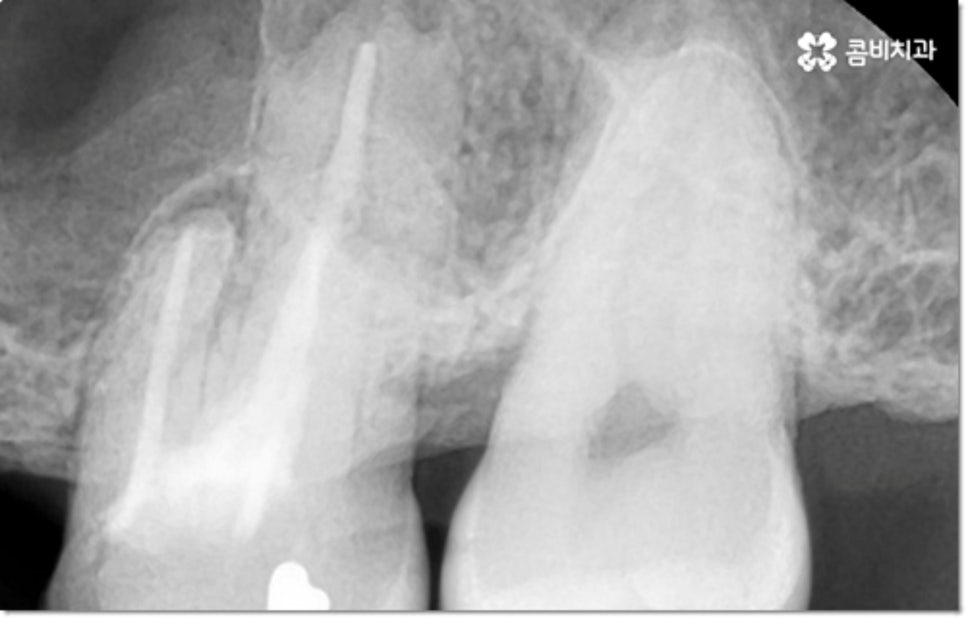

사진에서 볼 수 있는 사례는 아랫니가 크게 부러져서 빠졌을 때 아랫니임플란트 시술을 통해 수복을 해 준 거예요. 이때 빠른 일상 복귀를 원하는 만큼 기간이 얼마나 오래 걸리는가 하는 것은 임플란트 시술을 받으시는 분들의 가장 주된 관심사 중 하나라고 할 수 있는데요.

물론 갑자기 치아가 쑥 빠지거나 하는 것이 아니라 사진에서 볼 수 있듯이 치아 뿌리 끝부분이 둥글어지면서 짧아지는 정도이긴 하지만 아무래도 흔들림, 이시림 등의 불편함을 초래하고 치아와 잇몸을 약해지게 만들며 구강 건강 전체에 좋지 않은 영향을 줄 수 있으니 장기적으로 봤을 때도 이러한 습관은 바꾸시는 게 좋을 거예요.